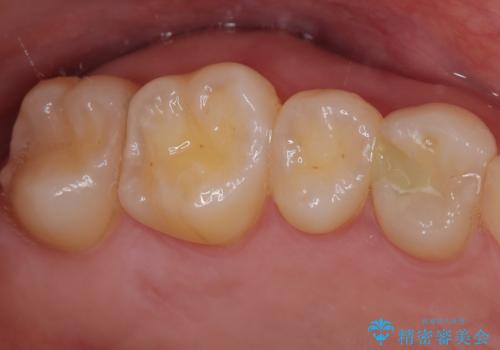

- 他院で虫歯を指摘され、精度の高い治療を希望されて来院された患者様です。

口腔内で直接処置を行う樹脂の材料(CR)で修復してありました。

フロスの引っ掛かりやレントゲン像から、CRを除去し、虫歯を徹底的に除去し、精度の高いセラミックインレーにて修復することとしました。